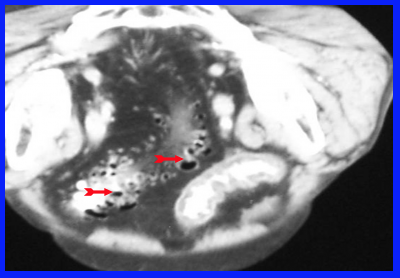

- טומוגרפיה ממוחשבת (CT) - מראה את הסעיפים עם בועות האוויר שבתוכם (תצלום 13.6) . בדלקת הסעיפים אפשר לראות כרכשת מעובה, ומורסות במקרה של התנקבות המוגבלת על-ידי האיברים שבסביבה. בחולים שהודגמו בהם מורסות, ניתן להחדיר מחט המונחית על-ידי טומוגרפיה ממוחשבת למורסה ולנקזה, ולאחר מכן להשאיר נקז להמשך הניקוז.

סיבוכי דלקת סעיפי הכרכשת ודלקת הצפק

האבחנה היא בטומוגרפיה ממוחשבת או באולטרה-סאונד שבהם אפשר להדגים את המורסה ולראות את המעי המעובה, חסר המבנה השקי (סקולרי) (תצלומים 14.6ו- 15.6).